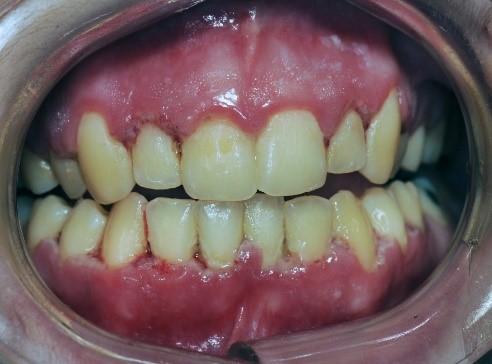

Appendix: Photo- and Radiographs of Periodontal Disease Associated With HIV

Photographs courtesy of Dr. Gwen Cohen Brown and the Dental Hygiene Department of New York City College of Technology

Figure 1: Patient with linear gingival erythema (LGE)

Figure 2: Patient with necrotizing ulcerative periodontitis (NUP)

Figure 3: Patient with linear gingival erythema (LGE) and necrotizing ulcerative periodontitis (NUP)

Figure 4: Patient with necrotizing ulcerative gingivitis (NUG)

Figure 5: Patient with localized bone loss